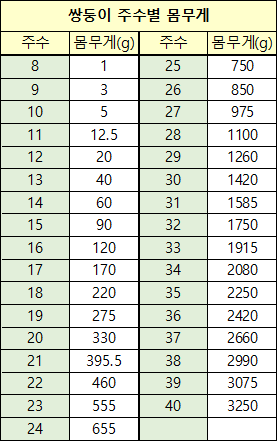

쌍둥이 기준 18주~19주 표준편차 평균 몸무게가 208g~284g 정도

세쌍둥이는 18주~19주 표준편차 평균 몸무게가 209g~276g 정도인데 다행히 몸무게는 잘나가는 듯하다.

참고문헌: Comparison of fetal growth in singleton, twin, and triplet pregnancies(Atsushi Kuno,1990)

세쌍둥이 임신 주수별 몸무게 차트는 잘 없어서 찾아본 논문인데 15, 16주의 쌍둥이 평균 몸무게가 세쌍둥이보다 현저히 적게 나가는 수치가 좀 이해가 안 되긴 한다. 오타가 났거나 수치가 잘못된 거 아닐까? 쌍둥이 52명, 세쌍둥이 12명을 대상으로 하여 표본이 많이 적긴 하다.